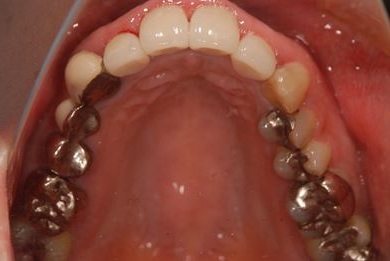

| 性別/年齢 | 女性 / 41歳 | ||||||||||||||||||||||||||||||||

| 治療方針 | セラミック治療にて、審美的回復を行う。 | ||||||||||||||||||||||||||||||||

| 治療内容 | エンプレスオールセラミッククラウン4本(オールセラミック用土台4本) | ||||||||||||||||||||||||||||||||